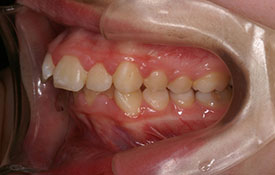

インビザラインの治療例:CASE-2

| プロフィール | 15歳 男性 |

| 所見 | アメリカから転院されて来られた方です。 インビザラインで上下顎の矯正治療を開始し下顎はアメリカで終了しており、上顎のみ治療の後期を担当しました。 アイライナーの装着は、1日平均22時間ほどでした。 |